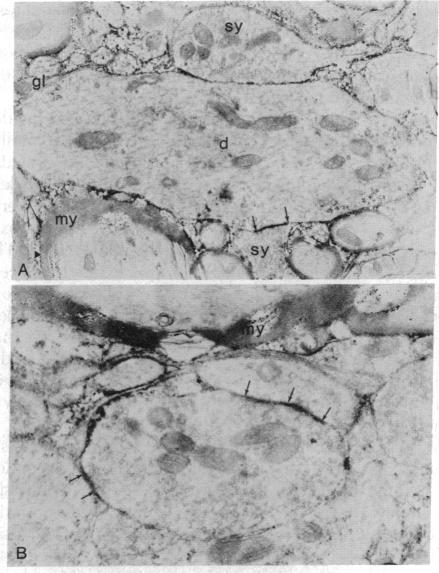

An immunoelectron microscopic method is described for sensitive high-resolution visualization of tissuebound cholera toxin. The principle is to incubate cells or tissue sections with toxin and then to localize the bound toxin with toxin-specific peroxidase (donor:hydrogen-peroxide oxidoreductase; EC 1.11.1.7)-conjugated antibody and enzyme substrate. Thin sections are examined for electron-opaque precipitates in a transmission electron microscope. Because of the specific binding of the toxin to membrane ganglioside G(M1), the method can be used for ultrastructural localization of this ganglioside. Semiquantitative data are obtained by titration of the limiting concentration of cholera toxin producing specific precipitates. The specificity of the method was controlled in various ways, including analyses of the correlation between the immunoelectron microscopy results and determinations of ganglioside G(M1) in tissues with different ganglioside concentrations, tissues hydrolyzed with Vibrio cholerae sialidase, tissues in which exogenous G(M1) has been incorporated, and lipid-extracted tissues. The immunoelectron microscopic method demonstrates that membrane G(M1) ganglioside is positioned on the external side exclusively. Cell-bound toxin remains in its original location on the plasma membrane surface of cells below 18 degrees , but appears to be redistributed both laterally and vertically in the membrane of cells incubated at 37 degrees for 30 min or longer. The results of this method indicate that in the central nervous system G(M1) is concentrated in the pre- and postsynaptic membranes of the synaptic terminals; a further increase in reactivity of these structures after hydrolysis of the nervous tissue with V. cholerae sialidase suggests that higher gangliosides of the same series are particularly increased in the pre- and postsynaptic junctions.